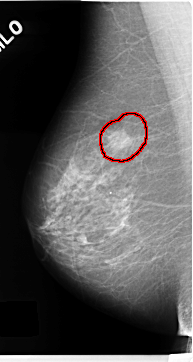

C_0128_1.RIGHT_MLO

FILE: C_0128_1.RIGHT_MLO.OVERLAY

TOTAL_ABNORMALITIES 1

ABNORMALITY 1

LESION_TYPE MASS SHAPE OVAL MARGINS MICROLOBULATED

ASSESSMENT 5

SUBTLETY 5

PATHOLOGY MALIGNANT

TOTAL_OUTLINES 1

BOUNDARY